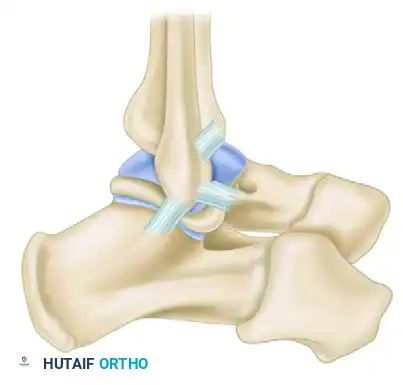

The Chrisman-Snook Modification

To address the persistent subtalar instability seen in the Watson-Jones procedure, Snook, Chrisman, and Wilson modified the Elmslie procedure. This technique uses a split half of the peroneus brevis tendon to reconstruct both the ATFL and CFL, restoring a more anatomical line of pull.

Biomechanical cadaveric studies confirm that the Chrisman-Snook reconstruction provides superior stability to the ankle joint complex compared to the Evans and Watson-Jones procedures, though it does result in a slight, permanent reduction in physiologic inversion motion.